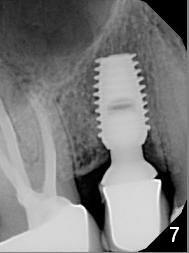

ZC is a 36-year-old man without significant medical history. His chief complaint is "I have Pain sometimes". His oral hygiene is poor (Fig.1). The tooth #3 has large MO caries with periapical radiolucency (*). The tooth #4 is non-salvageable (Fig.1,2). Four months after scaling & root planing, RCT and crown for #3 and extraction of #4 (Fig.3), a 5x8 mm Bicon implant is placed at the site of #4 (Fig.4). Peri-implant space is obliterated 5 months postop (Fig.5). The 2nd surgery is performed to uncover the implant and to place a temporary abutment. Two weeks later, a 5.0x.3.0 mm 0 degree Stealth Abutment 3.0 mm Post is placed (Fig.6). The most recent recall PA shows no bone loss for 5 years 3 months post cementation (Fig.7).